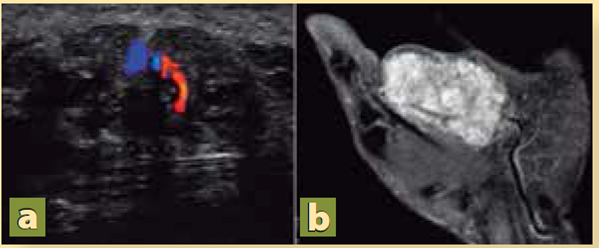

Se realizó ultrasonido Doppler de la mano, que reportó imagen multilobulada de 4.6 × 1.3 × 2.6 cm altamente vascularizado (Figura 2), por lo que se decidió realizar una angioresonancia magnética con la que se identificó una lesión heterogénea en la región palmar que involucraba de forma circunferencial a los tendones flexores del segundo, tercero y parcialmente cuarto dedos, con extensión hacia la región tenar; en la secuencia angiográfica presentó captación importante y heterogénea dependiente del plexo palmar, con múltiples imágenes vasculares en su interior (Figura 3). Con los hallazgos de imagen se decidió intervenir al paciente con el diagnóstico preoperatorio de lesión vascular en estudio.

Figura 2 a) Ultrasonido Doppler con imagen altamente vascularizada, con flujo alto. b) Angioresonancia magnética con hipercaptación de la lesión con componente venoso importante.